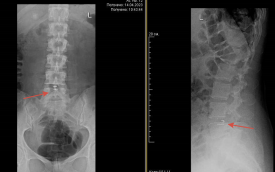

В Центр Илизарова обратилась пациентка с длительными болями в ноге. Исследования выявили у девушки грыжу межпозвоночного диска, сдавливающую нервный корешок. Консервативное лечение эффекта не давали.

В клинике пациентке провели операцию по удалению грыжи и протезированию фиброзного кольца (порванной оболочки диска) имплантатом «Barrikaid», сообщили в отделе маркетинга НМИЦ ТО им. акад. Г.А. Илизарова Минздрава РФ.

—  Специальные инструменты позволяют полностью удалить грыжу любого размера и расположения. Независимо от метода удаления грыжи, после операции в стенке диска остается отверстие, через которое может появиться новая грыжа, так называемый «рецидив». По данным разных источников, это происходит у 5-20% пациентов. Имплантат позволяет закрыть дефект диска и предотвратить рецидив , — рассказал врач-нейрохирург отделения №15 Центра Илизарова Олег Куликов .

Благодаря имплантату удаётся сохранить здоровую часть диска, замедлить развитие дегенеративного процесса.